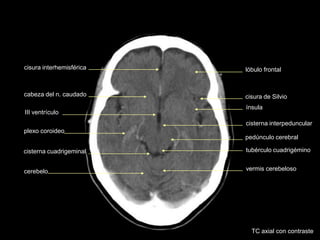

cisura interhemisférica

hipotálamo

plexo coroideo

asta temporal

IV ventrículo

lóbulo frontal

cisura de Silvio

ínsula

cisterna interpeduncular

pedúnculo cerebral

tubérculo cuadrigémino

cerebelo vermis cerebeloso

lóbulo occipital

TC axial con contraste